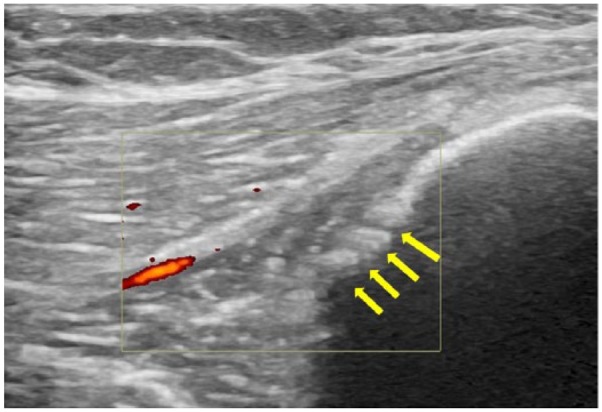

En esta imagen, se observan cambios periósticos (flechas amarillas), junto con un aumento del flujo en Doppler en esa misma zona, un hallazgo compatible con hiperemia o hipervascularización local.

¿Consigues ver las diferencias con respecto a la imagen anterior de una persona sana?